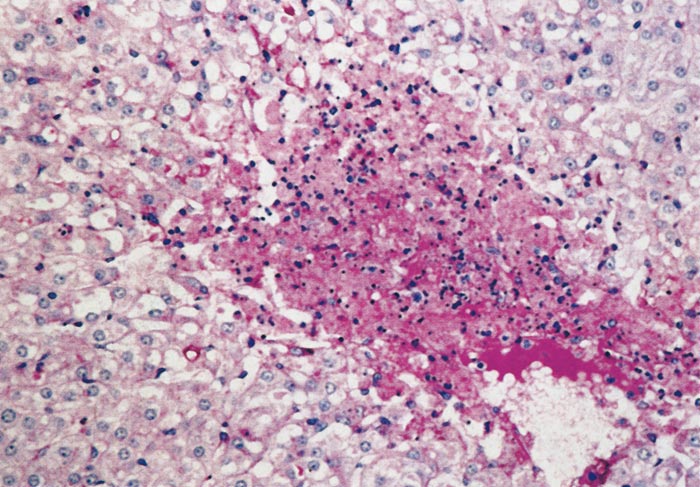

Lesions in target organs such as the liver in the acute disease are produced by the direct lytic effect of the virus on infected cells. In the liver of new-born lambs, for instance, there is initial cloudy swelling and hydropic degeneration of randomly scattered hepatocytes, which soon become necrotic as manifested by acidophilic cytoplasm and pyknotic nuclei. The lesions rapidly progress to form scattered primary necrotic foci of five to eight affected hepatocytes, with the presence of acidophilic cytoplasmic or apoptotic bodies resulting from cytolysis, and infiltration of neutrophils. As the primary lesions enlarge, numerous degenerated and necrotic hepatocytes and acidophilic bodies appear throughout the parenchyma. Ultimately there is massive necrotic hepatitis in which the residual primary foci can still be recognized as dense aggregates of cellular debris infiltrated by leukocytes.117, 168